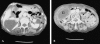

Torsion of the gallbladder is a rare entity that is difficult to diagnose preoperatively. The condition occurs most often in the elderly. Although its etiology is unknown, a constant finding is the presence of the gallbladder on a mobile mesentery (floating gallbladder). Torsion, or volvulus, of the gallbladder occurs when it twists axially, with the subsequent occlusion of bile and/or blood flow. Herein, a case of torsion of the gallbladder is presented where preoperative computed tomographic scan and laparoscopy were successfully used to diagnose and treat this condition without the usual requirement of open exploration. Given the possibility of laparoscopic cholecystectomy and the increasing incidence with which torsion of the gallbladder is being witnessed today, the importance of a preoperative computed tomographic scan is emphasized when there is a high index of clinical suspicion.